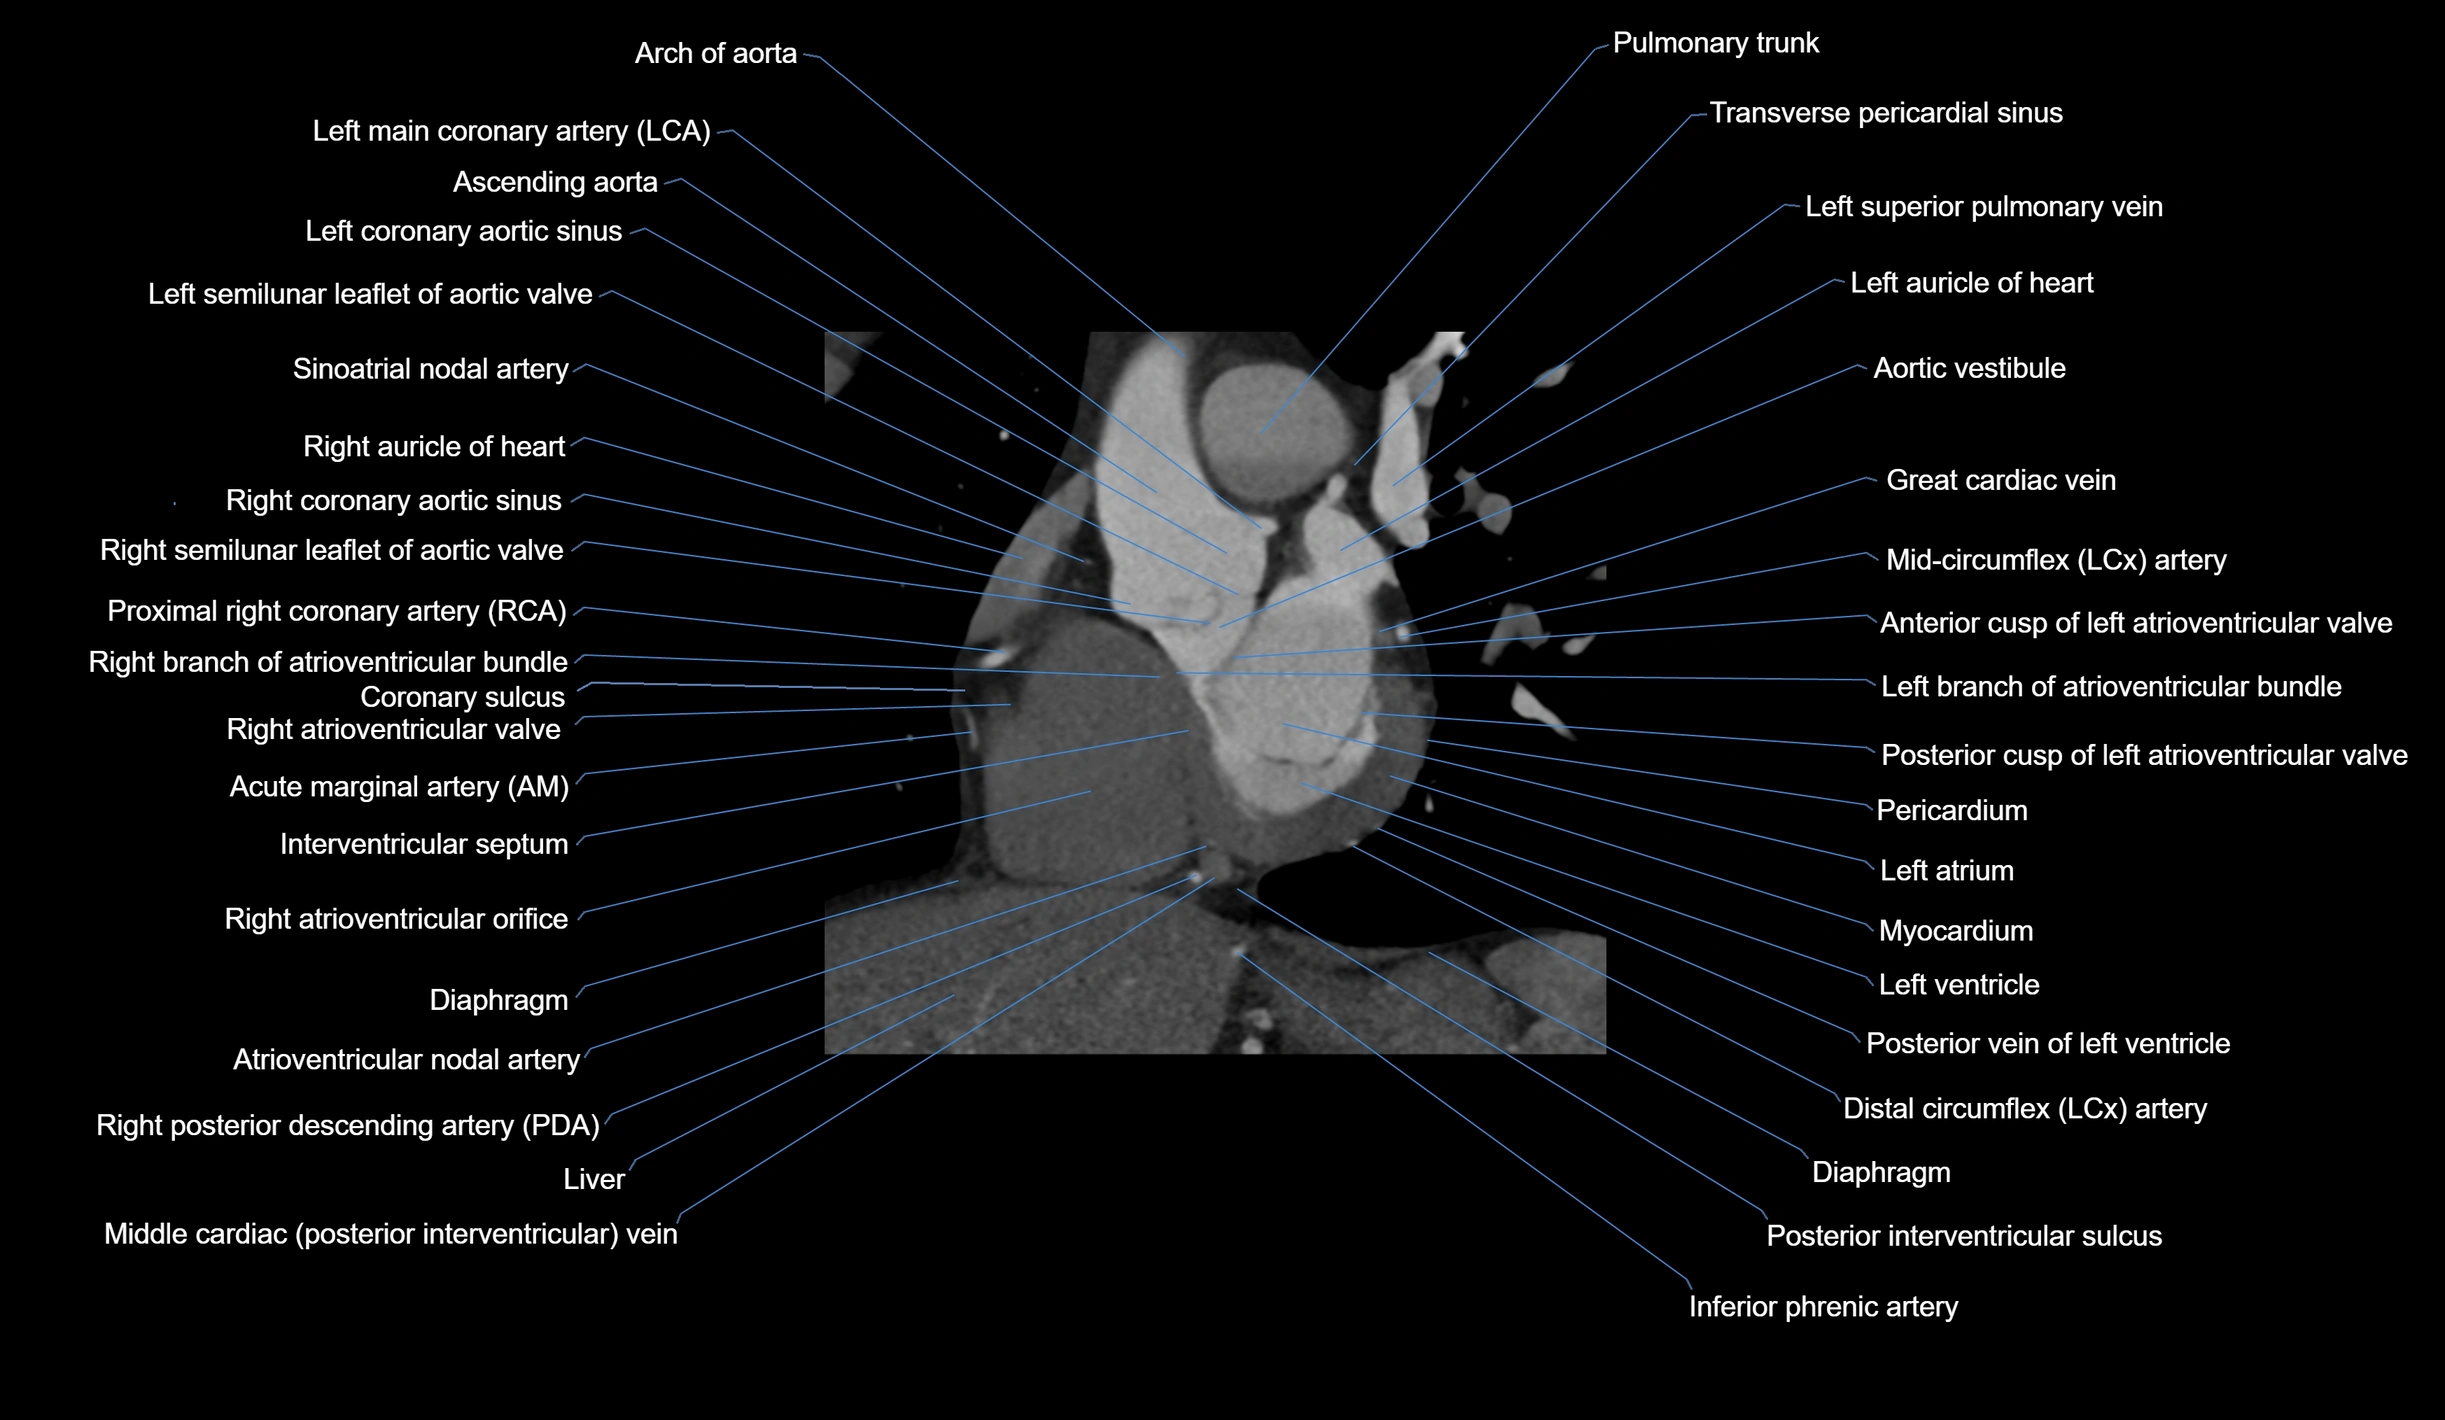

- Acute marginal artery (AM)

The acute marginal artery (AM) is one of the main branches of the right coronary artery (RCA). It typically arises from the mid to distal segment of the RCA and courses along the acute margin (right inferolateral border) of the right ventricle. The AM artery runs within the epicardial fat and supplies blood primarily to the right ventricular free wall.

The number and size of AM branches vary: most individuals have one dominant acute marginal artery, but some may have multiple smaller branches. The vessel is of high clinical importance in right ventricular infarction, since occlusion or disease of the RCA or AM branch can compromise right ventricular contractility and systemic venous return.

CT Appearance

CT Coronary Angiography (CCTA):

-

Best non-invasive modality for acute marginal artery visualization

Shows origin, course along the acute margin, and right ventricular branches

Detects stenosis, occlusion, calcified and non-calcified plaques, aneurysm, or anomalous course

Multiplanar reformats and 3D reconstructions help in pre-PCI and surgical planning

Critical for assessing right ventricular infarction risk in RCA disease

CT images